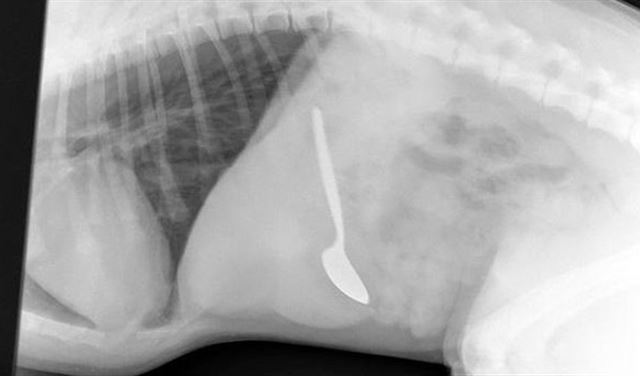

هكذا استخرج الأطباء "ملعقة" طولها 14 سم من معدة جرو!

تسبب جرو في ضجة بعد أن ابتلع ملعقة طعام صغيرة بطول أكثر من 14 سم. حيث كان الكلب المسمى، ثيودور، قد انتهى للتو من تناول طعام الغداء، عندها انتزع ملعقة من طاولة بالمطبخ وابتلعها.

استغرق الأمر بعض الوقت للعثور على الملعقة في أحشاء الجرو، ولم يكن ذلك بالهين بحسب الأطباء إذ تطلب "بعض المناورات".

وقد نفذت العملية في عيادة بيطرية في نورويتش، بمدينة نورفولك، في ولاية فرجينيا الأميركية، وسبقها أخذ الأشعة السينية.

كما تم تمرير منظار للمعدة من خلال الفم إلى أسفل لتحديد موضع الملعقة، ومن ثم استخدمت أدوات أخرى للمساعدة في استخراجها من داخل البطن وجرها.